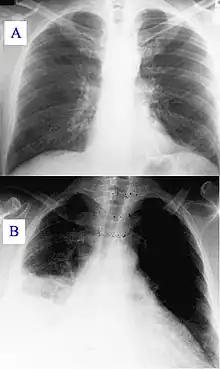

Image A: A normal chest X-ray Image B: Q fever pneumonia

Q fever was first described in 1935 by Edward Holbrook Derrick[39] in slaughterhouse workers in Brisbane, Queensland. The "Q" stands for "query" and was applied at a time when the causative agent was unknown; it was chosen over suggestions of abattoir fever and Queensland rickettsial fever, to avoid directing negative connotations at either the cattle industry or the state of Queensland.[40]